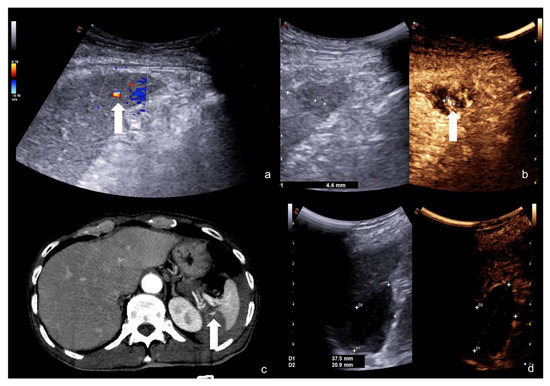

Beware of lacerated areas of the parenchyma (pseudo-nodular spared area). Always integrate with a preliminary CD–US study before CEUS examination (Figure 26).

Figure 26.

An example of possible pitfall at CEUS performed to follow-up a parenchymal laceration; in this case, a hepatic laceration. At CEUS examination, a nodular area of enhancement was visible within the hepatic laceration (a, dotted arrow), suspected for PSA; however, this finding was inconsistent with the preliminary CD–US evaluation, because the hepatic laceration area did not show any vascular pattern of PSA inside (b, white arrowhead). This finding was suspected for pseudo-nodular spared hepatic parenchyma and confirmed at biphasic contrast-enhanced CT examination (c, arterial phase, white arrow; d, venous phase, white arrow).

4.5. Step 5

Beware to the growing parenchymal collections in the suspicion of a vascular, biliary, or urinary leak (Figure 27).

Figure 27.

Post-traumatic laceration of the left hepatic lobe (a, white arrowhead) with evidence of surgical packing (asterisk); after surgical lobectomy, contrast-enhanced CT scan (b) showed a small fluid collection close to the biliary duct clipping (white arrow). Such collection increased in volume at follow-up CEUS examinations (c,d, respectively, 2 and 3 weeks after surgery, white arrows); this finding indirectly suggested a possible biliary leakage, although not directly viewable at CEUS (c,d, white arrows). This finding was confirmed at post-contrast hepatospecific phase fat-sat T1w MRI examination that showed biliary leak (e, arrowheads). Subsequent exclusion of the biliary leak with complete reabsorption of the biliary collection at CT examination (f, arrow).